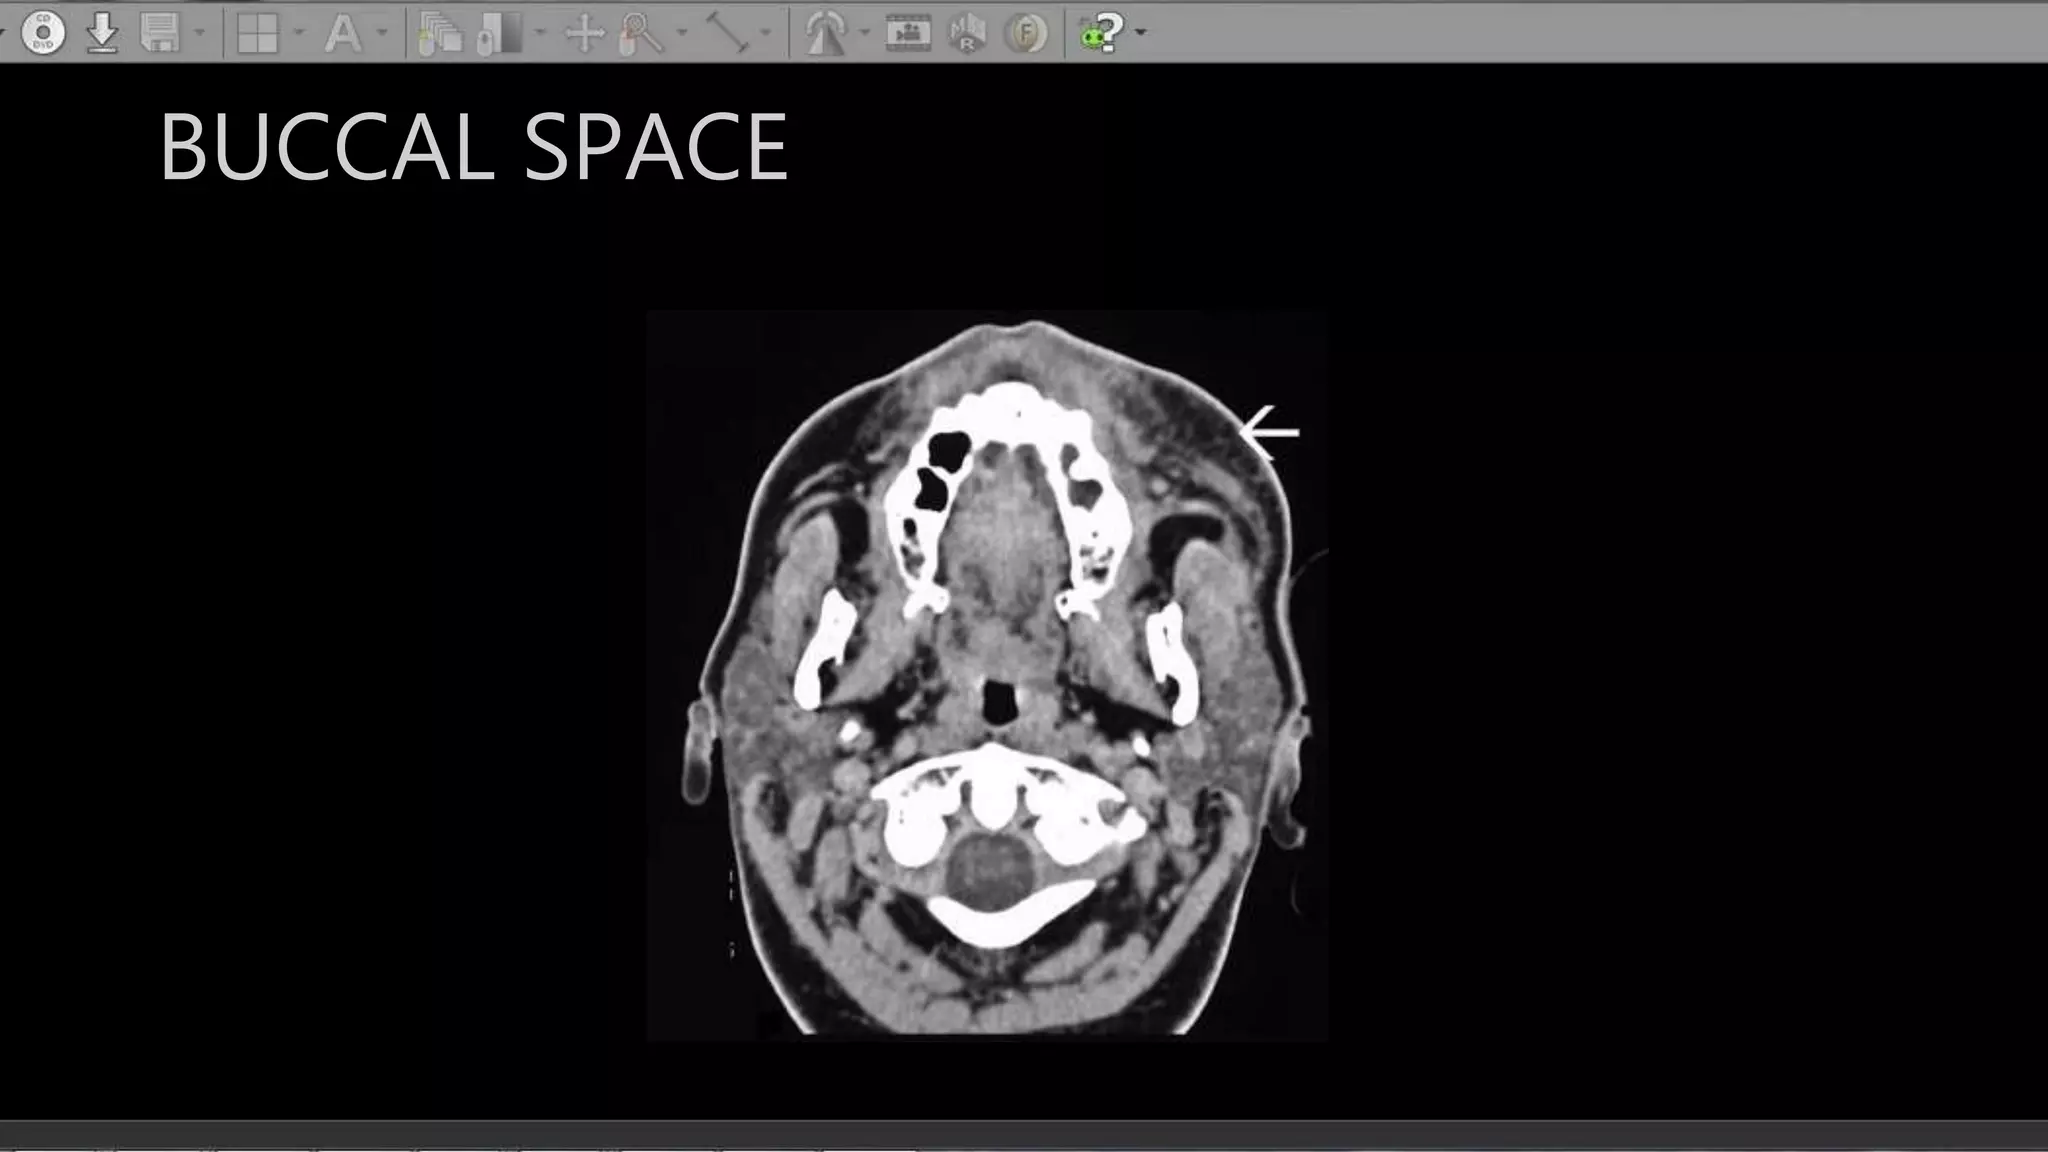

BUCCAL SPACE

• Extent : Medially - Buccinator

and max alveolar ridge

Post Laterally : Masticator space

• Contents: Buccal fat pad

BUCCAL SPACE • Extent: Medially - Buccinator and max alveolar ridge Post Laterally : Masticator space • Contents: Buccal fat pad